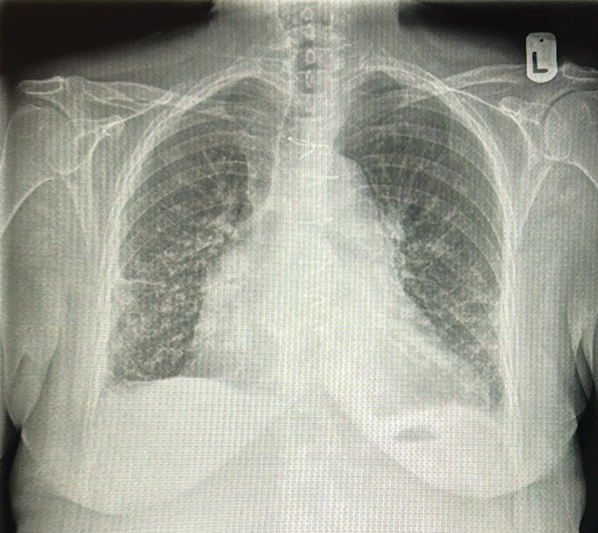

Aortic pseudoaneurysm occurs in 10 to 24% of patients after acute type A aortic dissection repair. We report the case of a 72-year-old female who developed an intraoperative iatrogenic ascending aortic dissection following mitral valve repair. A giant ascending aortic pseudoaneurysm was detected on follow-up imaging. This case emphasizes the importance of close radiological surveillance following acute aortic dissection repair.

Abstract Image